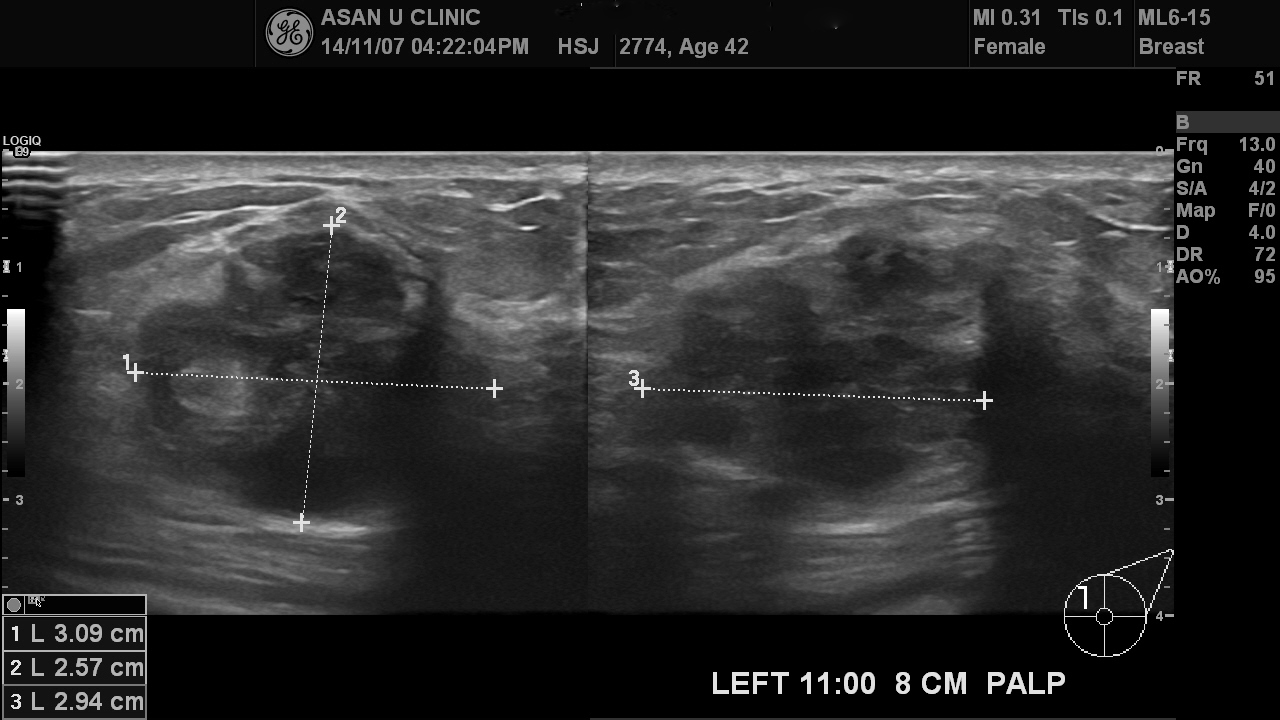

좌측 유방 상내측에 갑자기 만져지는 혹이 있어 내원한 42세 여성입니다.

초음파상 3cm이상의 혹이 있고 내부가 지저분한 에코를 보여

조직검사를 실시하였으며

안타깝게도 침윤성 유관암으로 진단되셨습니다.